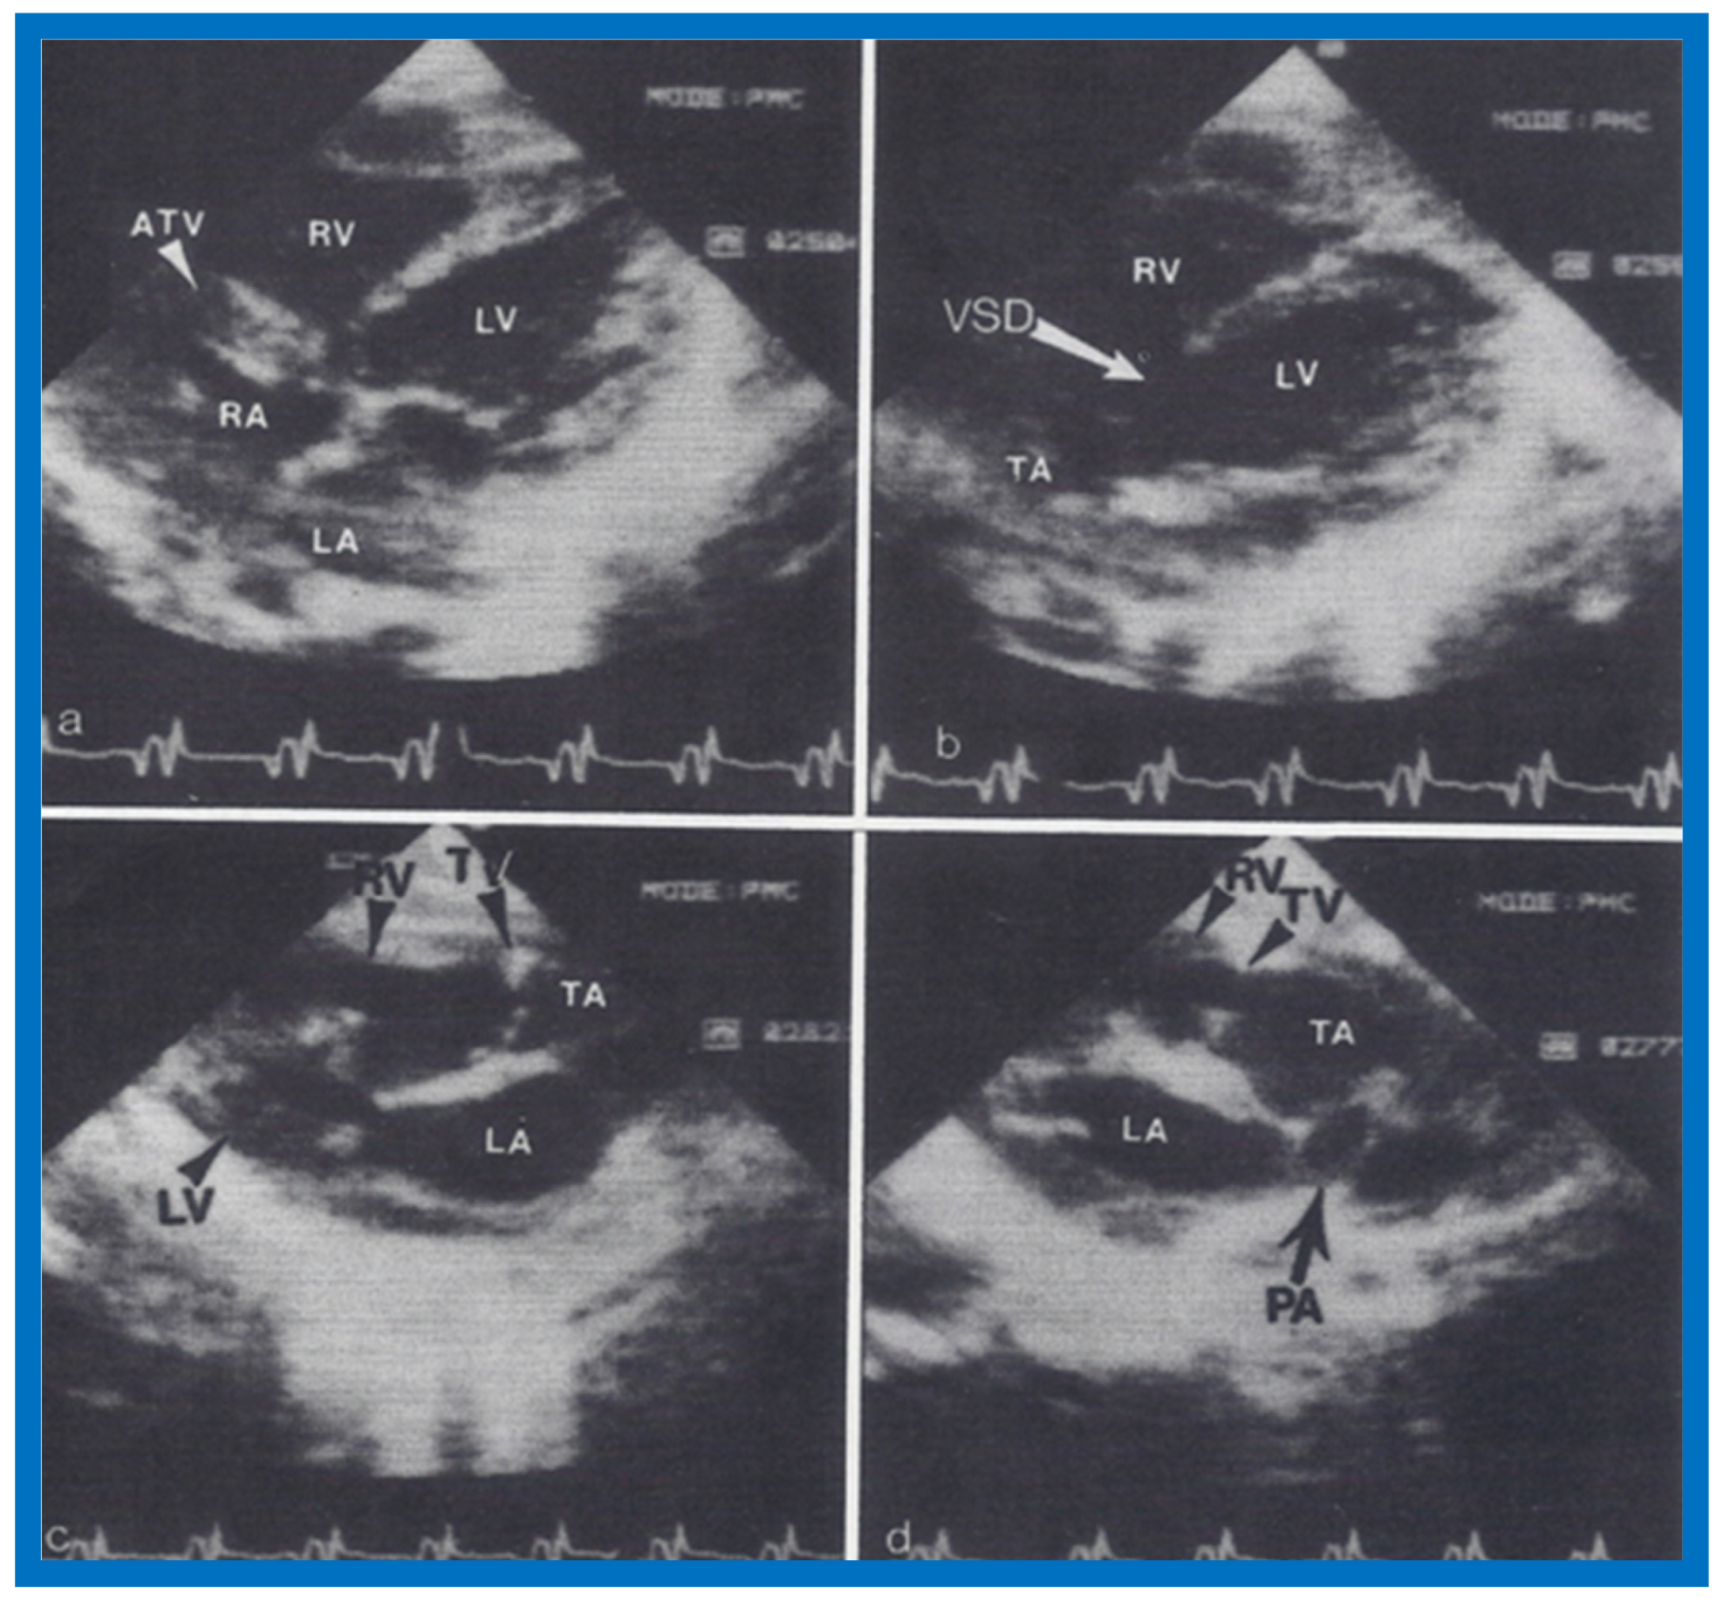

Figure 23.

Two-dimensional echocardiographic video frames demonstrating (a) atretic tricuspid valve (ATV) between the right atrium (RA) and right ventricle (RV), (b) a large subtruncal ventricular septal defect (VSD), (c) thickened and somewhat domed truncal valve (TV) leaflets, and (d) origin of the pulmonary artery (PA) from the posterior aspect of the truncus arteriosus (TA). LA, Left atrium; LV, left ventricle. Reproduced from Rao P.S., et al. [22].